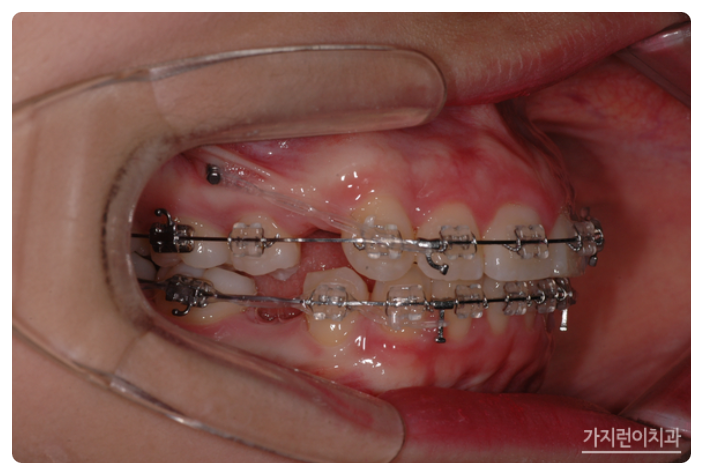

서울가지런이치과교정과 의원을 찾아주신 환자분의 모습인데요. 상악 돌출이 꽤나 심한 것을 볼 수 있습니다. 이런 경우에는 입술을 다무는 것이 어려운 정도였는데요. 전체적으로 치아를 후방으로 이동할 필요가 있어 돌출입 교정과 거미스마일 교정을 진행하게 되었습니다.

서울가지런이치과 교정과 의원, 강남에서도 거미스마일과 돌출입 치아교정이 이루어지고 있었는데요. 충분한 치아이동 공간을 확보하기 위해 상하악 1소구치를 발치한 후에 상악 잇몸뼈에 미니스크류를 식립해 효과적으로 힘을 주어 치아를 이동시켰습니다. 미니스크류를 진행하게 되면 상악 전치의 후방 이동이 일어나면서 상악 전치를 위로 합입시킬 수 있는데요. 상악이 어느 정도 이동한 것을 확인한 후에 하악에도 미니스크류를 식립해 상하악 전치를 동시에 후방으로 이동시킬 수 있었습니다.